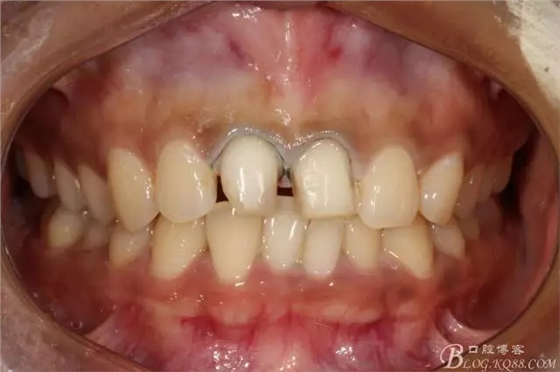

2016.1復(fù)查情況很不好,再次建議做瓷貼面并告知各自優(yōu)缺點(diǎn)。這回患者同意并選擇鑄瓷貼面。

11扭轉(zhuǎn)明顯,擔(dān)心備牙過多,所以選取了一個(gè)模型,在石膏模型上先試備后,感覺還行。

備牙后11(因扭轉(zhuǎn)制牙有點(diǎn)多,還是露牙本質(zhì)了)